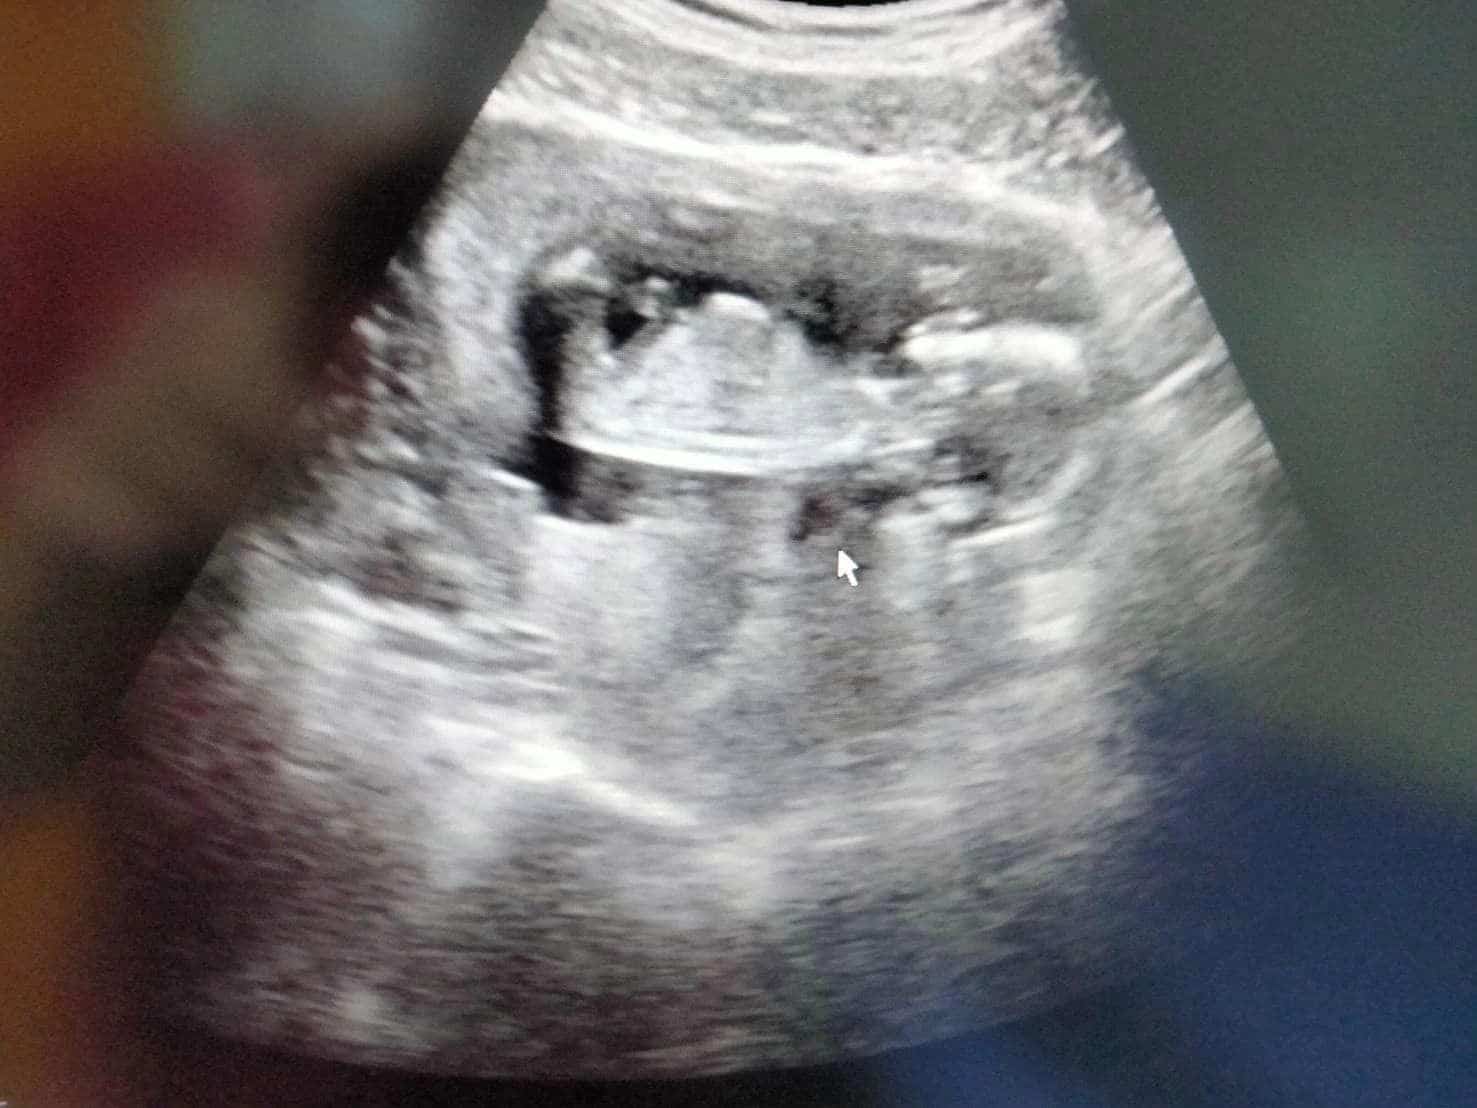

“โสรยา พรมหล้า” ยืนยันเอง ท้องแล้ว อวดภาพอัลตราซาวด์ 3 เดือน

โสรยา พรมหล้า มือเซตทีมชาติไทย ยืนยันเอง ข่าวตั้งครรภ์ โพสต์ภาพอัลตราซาวด์ ท้อง 3 เดือน แฟน ๆ ร่วมแสดงความยินดีคับคั่ง

วันนี้ 30 กรกฎาคม 2566 นับเป็นข่าวใหญ่น่ายินดีของวงการวอลเลย์บอล โสรยา พรมหล้า เซตเตอร์ทีมชาติไทย ออกมาโพสต์ยืนยันข่าวดีด้วยตนเอง ว่าตั้งครรภ์ได้ 3 เดือนแล้ว หลังจากก่อนหน้านี้ประกาศว่าจะกลับไปอยู่บ้านเกิด เชียงราย 1 ปี

ล่าสุด โสรยาได้โพสต์ผ่านเฟซบุ๊กส่วนตัว Promla Soraya ถึงข่าวน่ายินดีนี้ ระบุว่าอายุครรภ์ได้ 3 เดือนแล้ว พร้อมแนบภาพอัลตราซาวด์เป็นหลักฐาน

“เบบี๋ 3 เดือนกว่าแล้วววว